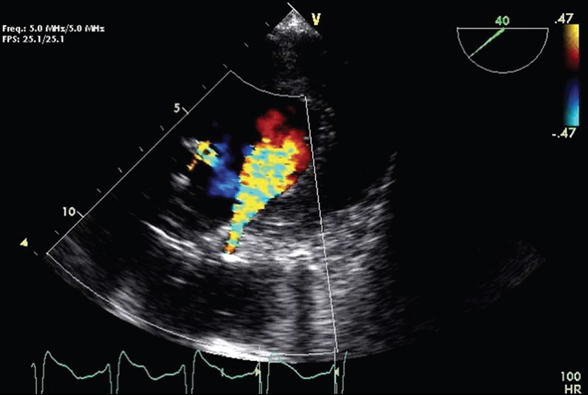

Aortic valve replacement is a procedure in which a patient's failing aortic valve is replaced with an artificial heart valve. The aortic valve can be affected by a range of diseases; the valve can either become leaky (aortic insufficiency / regurgitation) ... Read Article

Percutaneous aortic valve replacement - Wikipedia, The Free ...

Percutaneous aortic valve replacement (PAVR), also known as transcatheter aortic valve implantation (TAVI) or transcatheter aortic valve replacement (TAVR), is the replacement of the aortic valve of the heart through the blood vessels (as opposed to valve replacement by open heart surgery). ... Read Article